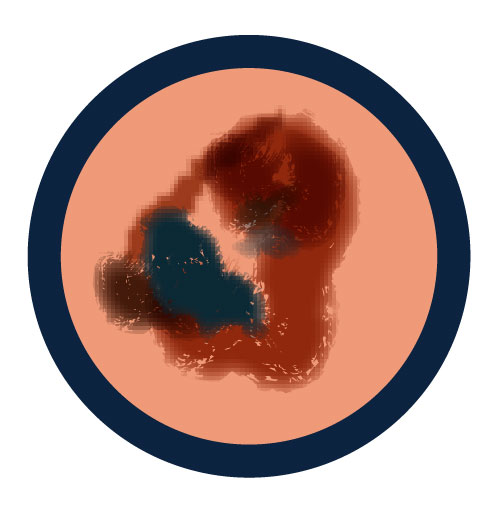

Signs of cancerous moles

A new spot on the skin or a spot that is changing in size, shape or color, or one that looks different, is an important warning sign of melanoma and should be checked by a doctor. The ABCDE rule outlines the characteristics of moles that may be melanoma and is helpful guidance for monitoring skin changes:

A is for Asymmetry

One half of a mole or birthmark does not match the other.

B is for Border

The edges are irregular, ragged, notched or blurred.

C is for Color

The color is not the same all over and may include different shades of brown or black, or sometimes with patches of pink, red, white, or blue.